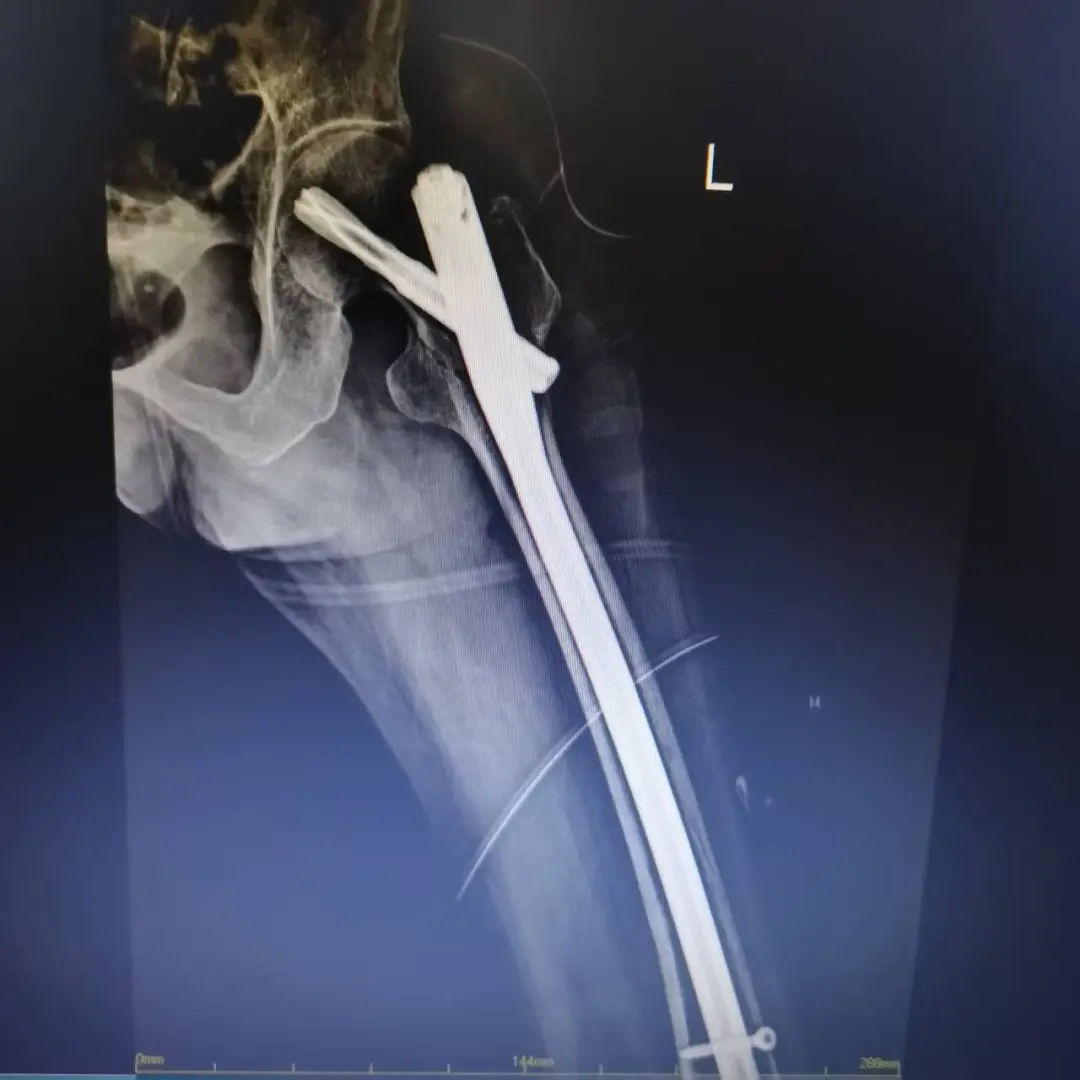

經(jīng)過系統(tǒng)術(shù)前調(diào)理,患者電解質(zhì)紊亂得到糾正,心功能趨于穩(wěn)定。在多學(xué)科團(tuán)隊(duì)評估后,最終排除絕對手術(shù)禁忌癥,確定手術(shù)方案為“左側(cè)股骨髓內(nèi)針內(nèi)固定術(shù)”。該術(shù)式創(chuàng)傷小、固定牢,利于患者早期活動,非常適合高齡患者。

手術(shù)當(dāng)日,麻醉醫(yī)師實(shí)施精準(zhǔn)麻醉并全程嚴(yán)密監(jiān)護(hù),骨科主任王曉楓帶領(lǐng)手術(shù)團(tuán)隊(duì)成功實(shí)施髓內(nèi)釘固定。手術(shù)過程順利,出血量少,患者安返病房。